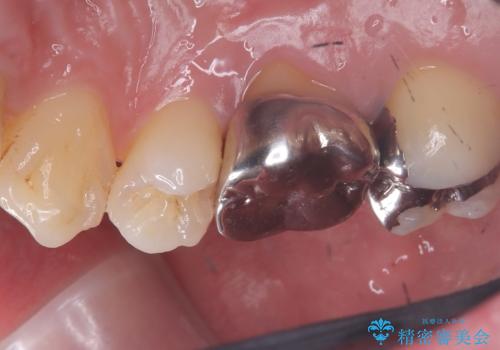

右上6番目の歯の被せものと歯質の境目に大きな窪みが出来ており、そこに汚れが停滞しやすい状態で虫歯もそこから広がっていたため、被せもののやり替えと必要に応じて土台の立て直しも行うこととしました。

メタルクラウンを除去したところ近心面に大きな窪みとう蝕を認め、ファイバ-コアからのやり替えとしました。クラウンは審美性の良いセラミッククラウンを選択されました。